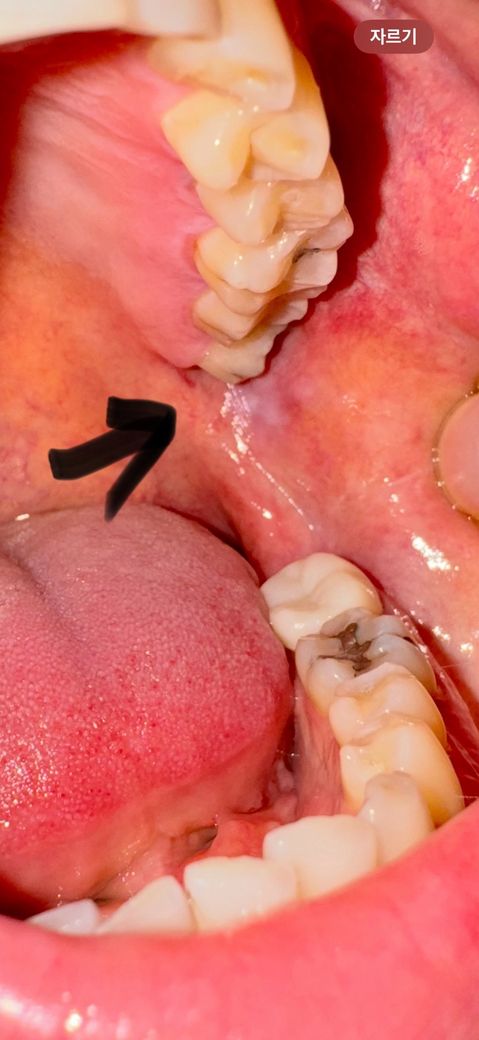

어금니쪽 볼에 하얀게 있는데 이게뭘까요

3일전 아침에 양치하고나서

통증이 있었어요.

밥먹을때 아플정도로 사진부분이 아팠고,

그다음날부터는 통증은 아예없어졌는데요

지금보니까 사진처럼 하얗게 되어있는데

원래이런건가요?

그리고 그 부분에 사랑니가 옆으로 자라서

가끔 찌르는듯 통증이있을때가있는데요

사랑니를 발치해야할까요?

1. 사진 화살표부분은 염증인가요?

2. 그부분을 자꾸 사랑니가 찌르는데 뽑아야하나요?

사진에 보이는 건 사랑니 때문에 볼살이 자극을 받아서 생긴거 같습니다. 사랑니 발치는 단순 발치라 어렵지 않을것같습니다.

볼이 씹혀서 생기는 것으로 예상되며 사랑니를 발치하시면 호전될 것 같습니다. 빼는 게 좋습니다.

1. 초기 염증으로 보이며 해당 부위의 사랑니가 볼쪽으로 나 있어 볼쪽 잇몸을 지속적으로 자극하는 것으로 보입니다.

2. 현재 상태에서는 뽑는 것이 좋습니다.

3. 마취를 하면 대부분 통증이 없으나 통증의 정도는 사람마다 다를 수 있습니다.

1. 비스듬히 맹출한 사랑니 때문에 잇몸과 볼살이 자극되는 것 같습니다

2. 마취만 잘 되면 이 뺄때 안아픕니다

사랑니로 인해서 점막조직이 자극이 되다보면 해당부위가 하얗게 변할수 있습니다 또한 손상으로 인해서 통증이 생길수도 있습니다. 사랑니로 인해서 주변조직에 문제를 발생시킨다면 사랑니를 발치해 주는것이 좋습니다.